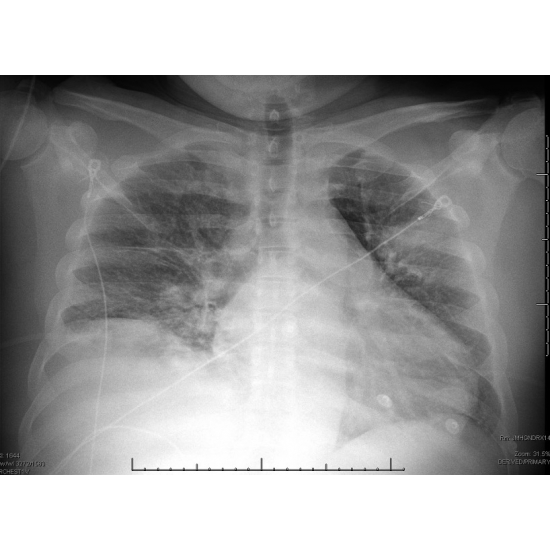

EKG demonstrated rightward axis and incomplete right bundle branch block. Echo found an EF of 60-65%, normal LV wall motion, moderate concentric LV hypertrophy, and mild to moderate dilation of the RV. Chest X-ray was notable for right pleural effusion, ill-defined airspace opacity in the left upper and mid lung zones, possibly an infectious/inflammatory process, cannot exclude neoplasm. Case Photo #1 CTA chest with contrast demonstrated 5.6cm x 5.4 mass causing severe narrowing of left upper lobe segmental pulmonary artery branches, as well as nodules. Case Photo #2 Thoracentesis was performed, and pleural fluid cultures were negative for growth, and cytology was negative for malignancy. Repeat CT chest with contrast done 11 days later showed a decrease in mass to 3.3 x 2.7 cm. Case Photo #3